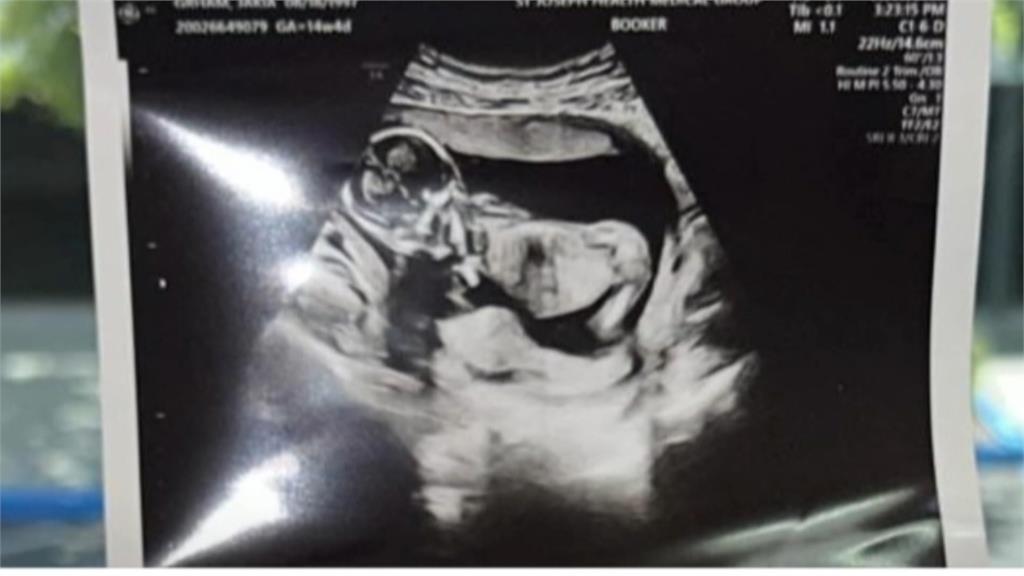

一對同志網紅,日前高調在社群分享,在墨西哥分別找了兩個代理孕母,各生下一對雙胞胎,還強調他們此前完全沒育兒經驗,引發輿論炸鍋!網友批評這對情侶,忽視代理孕母付出,根本買小孩賺流量,隨著風波愈演愈烈,沒想到又有人,上傳代理孕母無碼分娩影片被炎上!

Po出影片的男子,被起底是慈濟醫院的吳姓骨科醫師,對此,慈濟醫院表示,這是醫師私領域個人行為,要妥善面對與處理。吳姓骨科醫師聲稱影片都有經過孕母同意,說自己的基因不是特別好,只是個愛孩子的普通人。但自曝當初醫生曾建議幫小孩做檢查時都被他回絕,還說產檢的時候正常,有什麼好做的?讓網友看不下去,直呼無法想像是何等的自大與高傲,才會找代孕還把孕母分娩的影片發出來、跟拍動物生產畫面一樣。